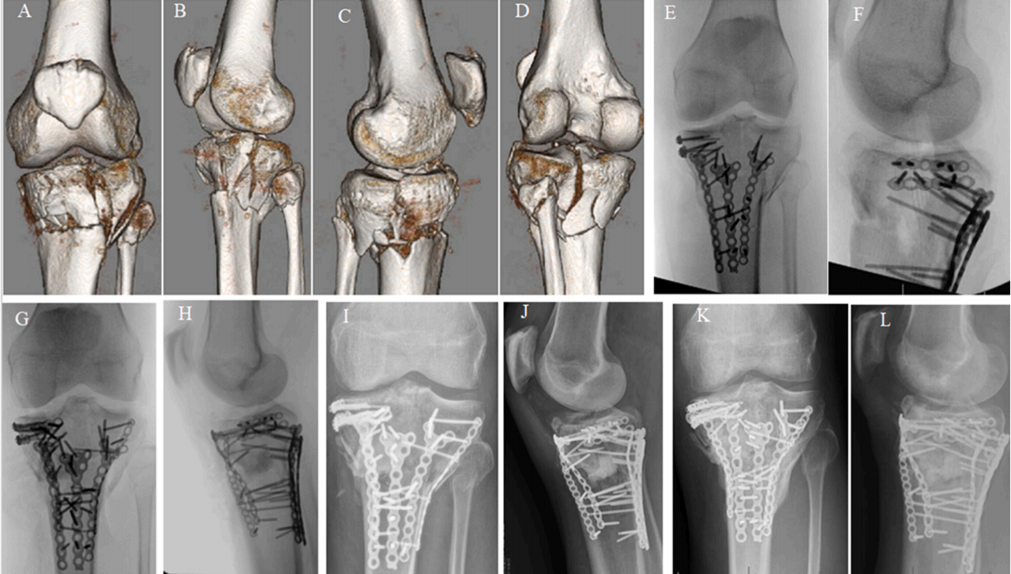

A-D) 54 岁女性患者多髁平台骨折(包括前外侧、外侧、前内侧和后内侧骨折)的 3D CT 扫描。 E-J) 术中 C 臂机 X 光片显示复位和固定的顺序。 J, K) 术后 24 周随访 X 光片显示骨折愈合且固定稳定。